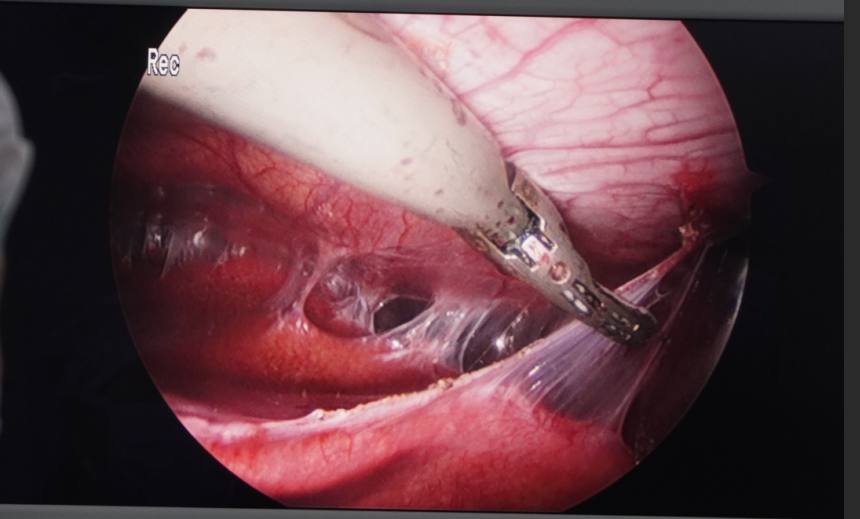

手术如期进行。当腹腔镜探入患者腹腔时,眼前的景象印证了术前的预判:腹腔内大片紧密粘连,胆囊区域完全被包裹成一片“无人区”,正常的解剖标志根本无从寻觅。特别是由于胆囊陷入肝脏,传统的“先显露胆囊三角”的方法已行不通。

面对如此棘手的状况,主刀医生果断调整策略,采取 “顺藤摸瓜、逆向剥离” 的安全术式。手术团队以胆囊底部作为突破口,从胆囊陷入肝脏的“顶部”开始,利用精细的超声刀,像考古学家清理文物一样,一点点地分离粘连,沿着胆囊的走行,小心翼翼地向着胆囊三角区域“顺藤摸瓜”进行游离。

在分离过程中,由于胆囊嵌顿在器官之间,胆管、肝总管的位置难以确认,每一步都如履薄冰。医生凭借丰富的解剖知识和稳定的手感,在粘连的“荆棘”丛中精准地找到了胆囊管与胆囊动脉。在完全确认胆总管走行无误后,医生予以妥善夹闭并离断。整个操作过程出血少,成功保留了肝脏及周围脏器的完整性,避免了中转开腹。